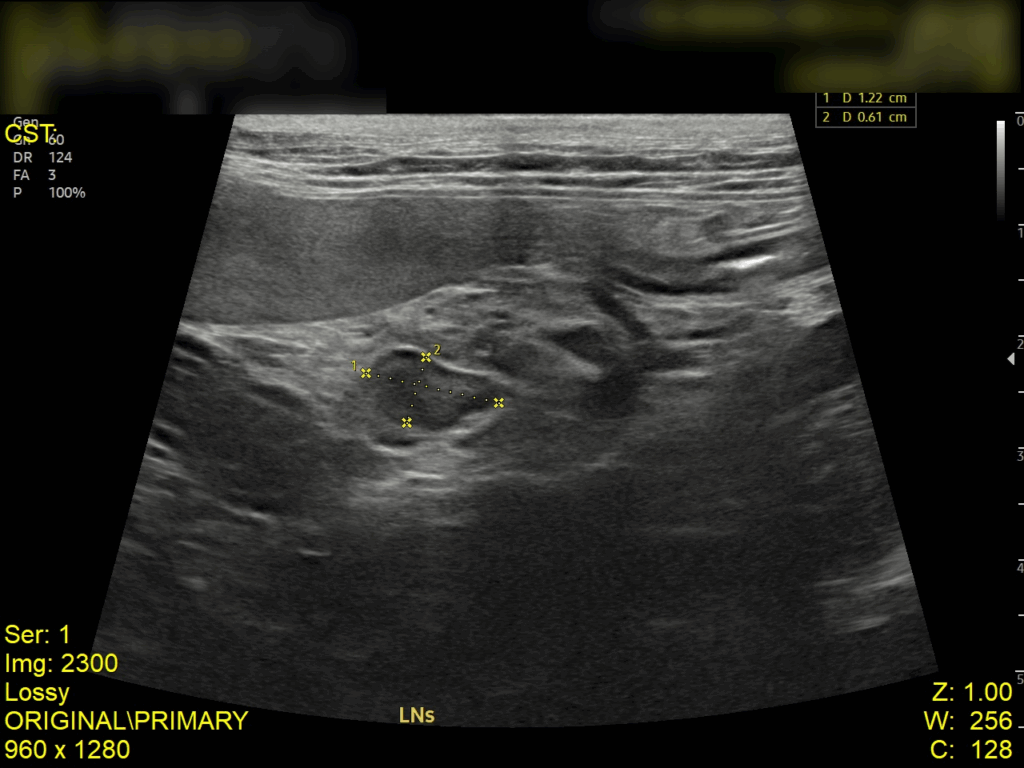

복부 초음파 검사 결과

초음파 검사 결과, 복강 내 림프절이 비대된 모습이 확인되었고, 장벽 두께가 정상보다 두꺼워진 것을 확인되었습니다. 이는 장 내 염증 반응이나 감염성 원인에 의해 장벽이 자극을 받고 있음을 의미합니다.